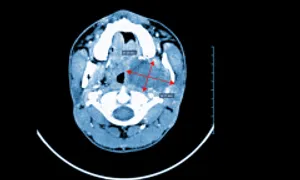

Bác sĩ chụp MRI vùng đầu mặt có tiêm thuốc cản quang để quan sát rõ khối u. Kết quả cho thấy u nằm trong khoang cảnh bên trái, sâu trong xương hàm dưới, kích thước khoảng 5,2x4,9x3,4 cm. Khối u có bờ đều, tiên lượng lành tính cao. Tuy nhiên, u của người bệnh lớn hơn 3 cm và nằm tại khu vực khoang cảnh, dễ chèn ép các cơ quan liên quan như đường thở, đường ăn làm ảnh hưởng đến động và tĩnh mạch cảnh, dây thần kinh sọ não...

Ảnh khối u khoang cảnh trên phim chụp cộng hưởng từ. Ảnh: Bệnh viện Tâm Anh